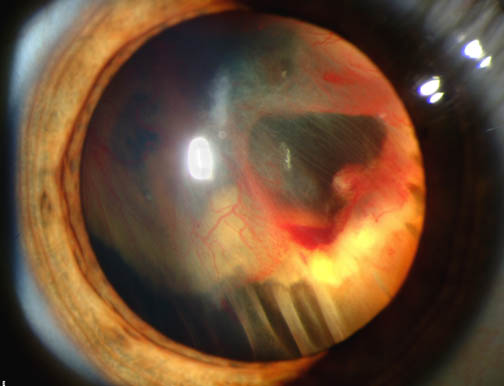

Retinal detachment clinical photograph.

Retinal Detachment

A detached retina is a medical emergency that often requires urgent surgery.

• Retinal detachment: National Eye Institute (NIH), public domain. Source